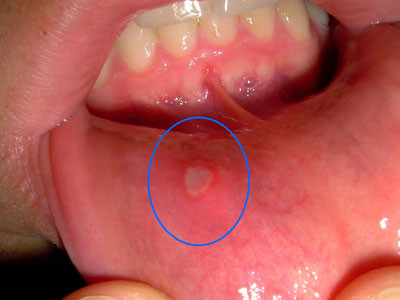

7. Chữa lợi và niêm mạc lở loét, lưỡi rộp: Vỏ ốc 2 cái, cỏ nhọ nồi 50g. Vỏ ốc sao với cát, tán mịn; cỏ nhọ nồi sấy khô, tán bột. Trộn đều hai thứ bột. Xát vào răng lợi nhiều lần trong ngày. Ảnh: yhoccongdong.com.